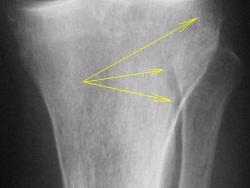

4. При анализе проксимального эпи-метафиза б/берцовой кости, локальные участки остеопороза, отмеченные стрелками, связаны, по всей видимости, именно с функциональной недостаточностью мениска и связки, а также с наличием феморо-пателлярного артроза, что функционально выразилось в "недогрузе" латеральных отделов коленного сустава, (возможно даже из-за болевого синдрома, не исключается "подсознательная разгрузка"), и переносе "нагрузки на медиальные отделы.

Конечно, можно предположить, что повреждающий фактор (альтерация) действовал, как показано стрелками, т.е. первопричиной все-таки была какая-то травма (надо объяснить контактность поражения). А можт быть это не остеохондропатия?